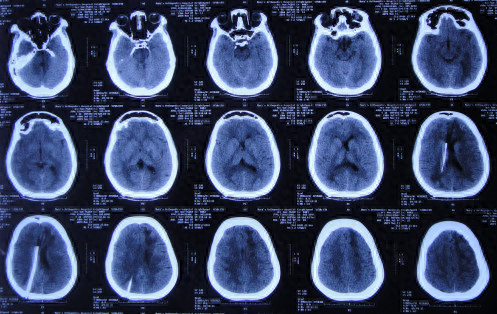

一、李小勇脑脊液科入院前病史

图-2:2019年2月12日头颅核磁

图-3:2019年2月13日头颅核磁